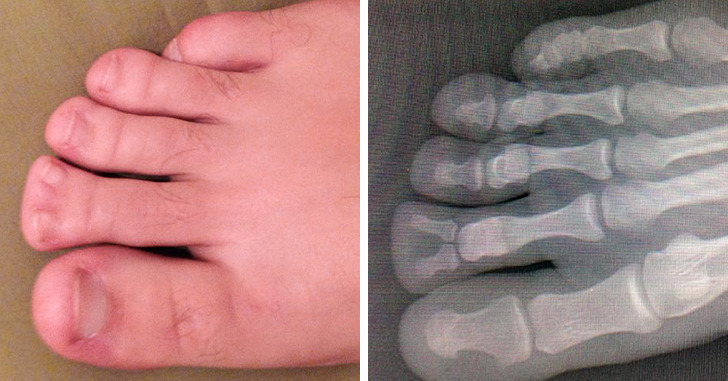

9. “Este é o meu pé. Há 22 anos que quero ver um raio-X dele. Achei que você também gostaria de ver”